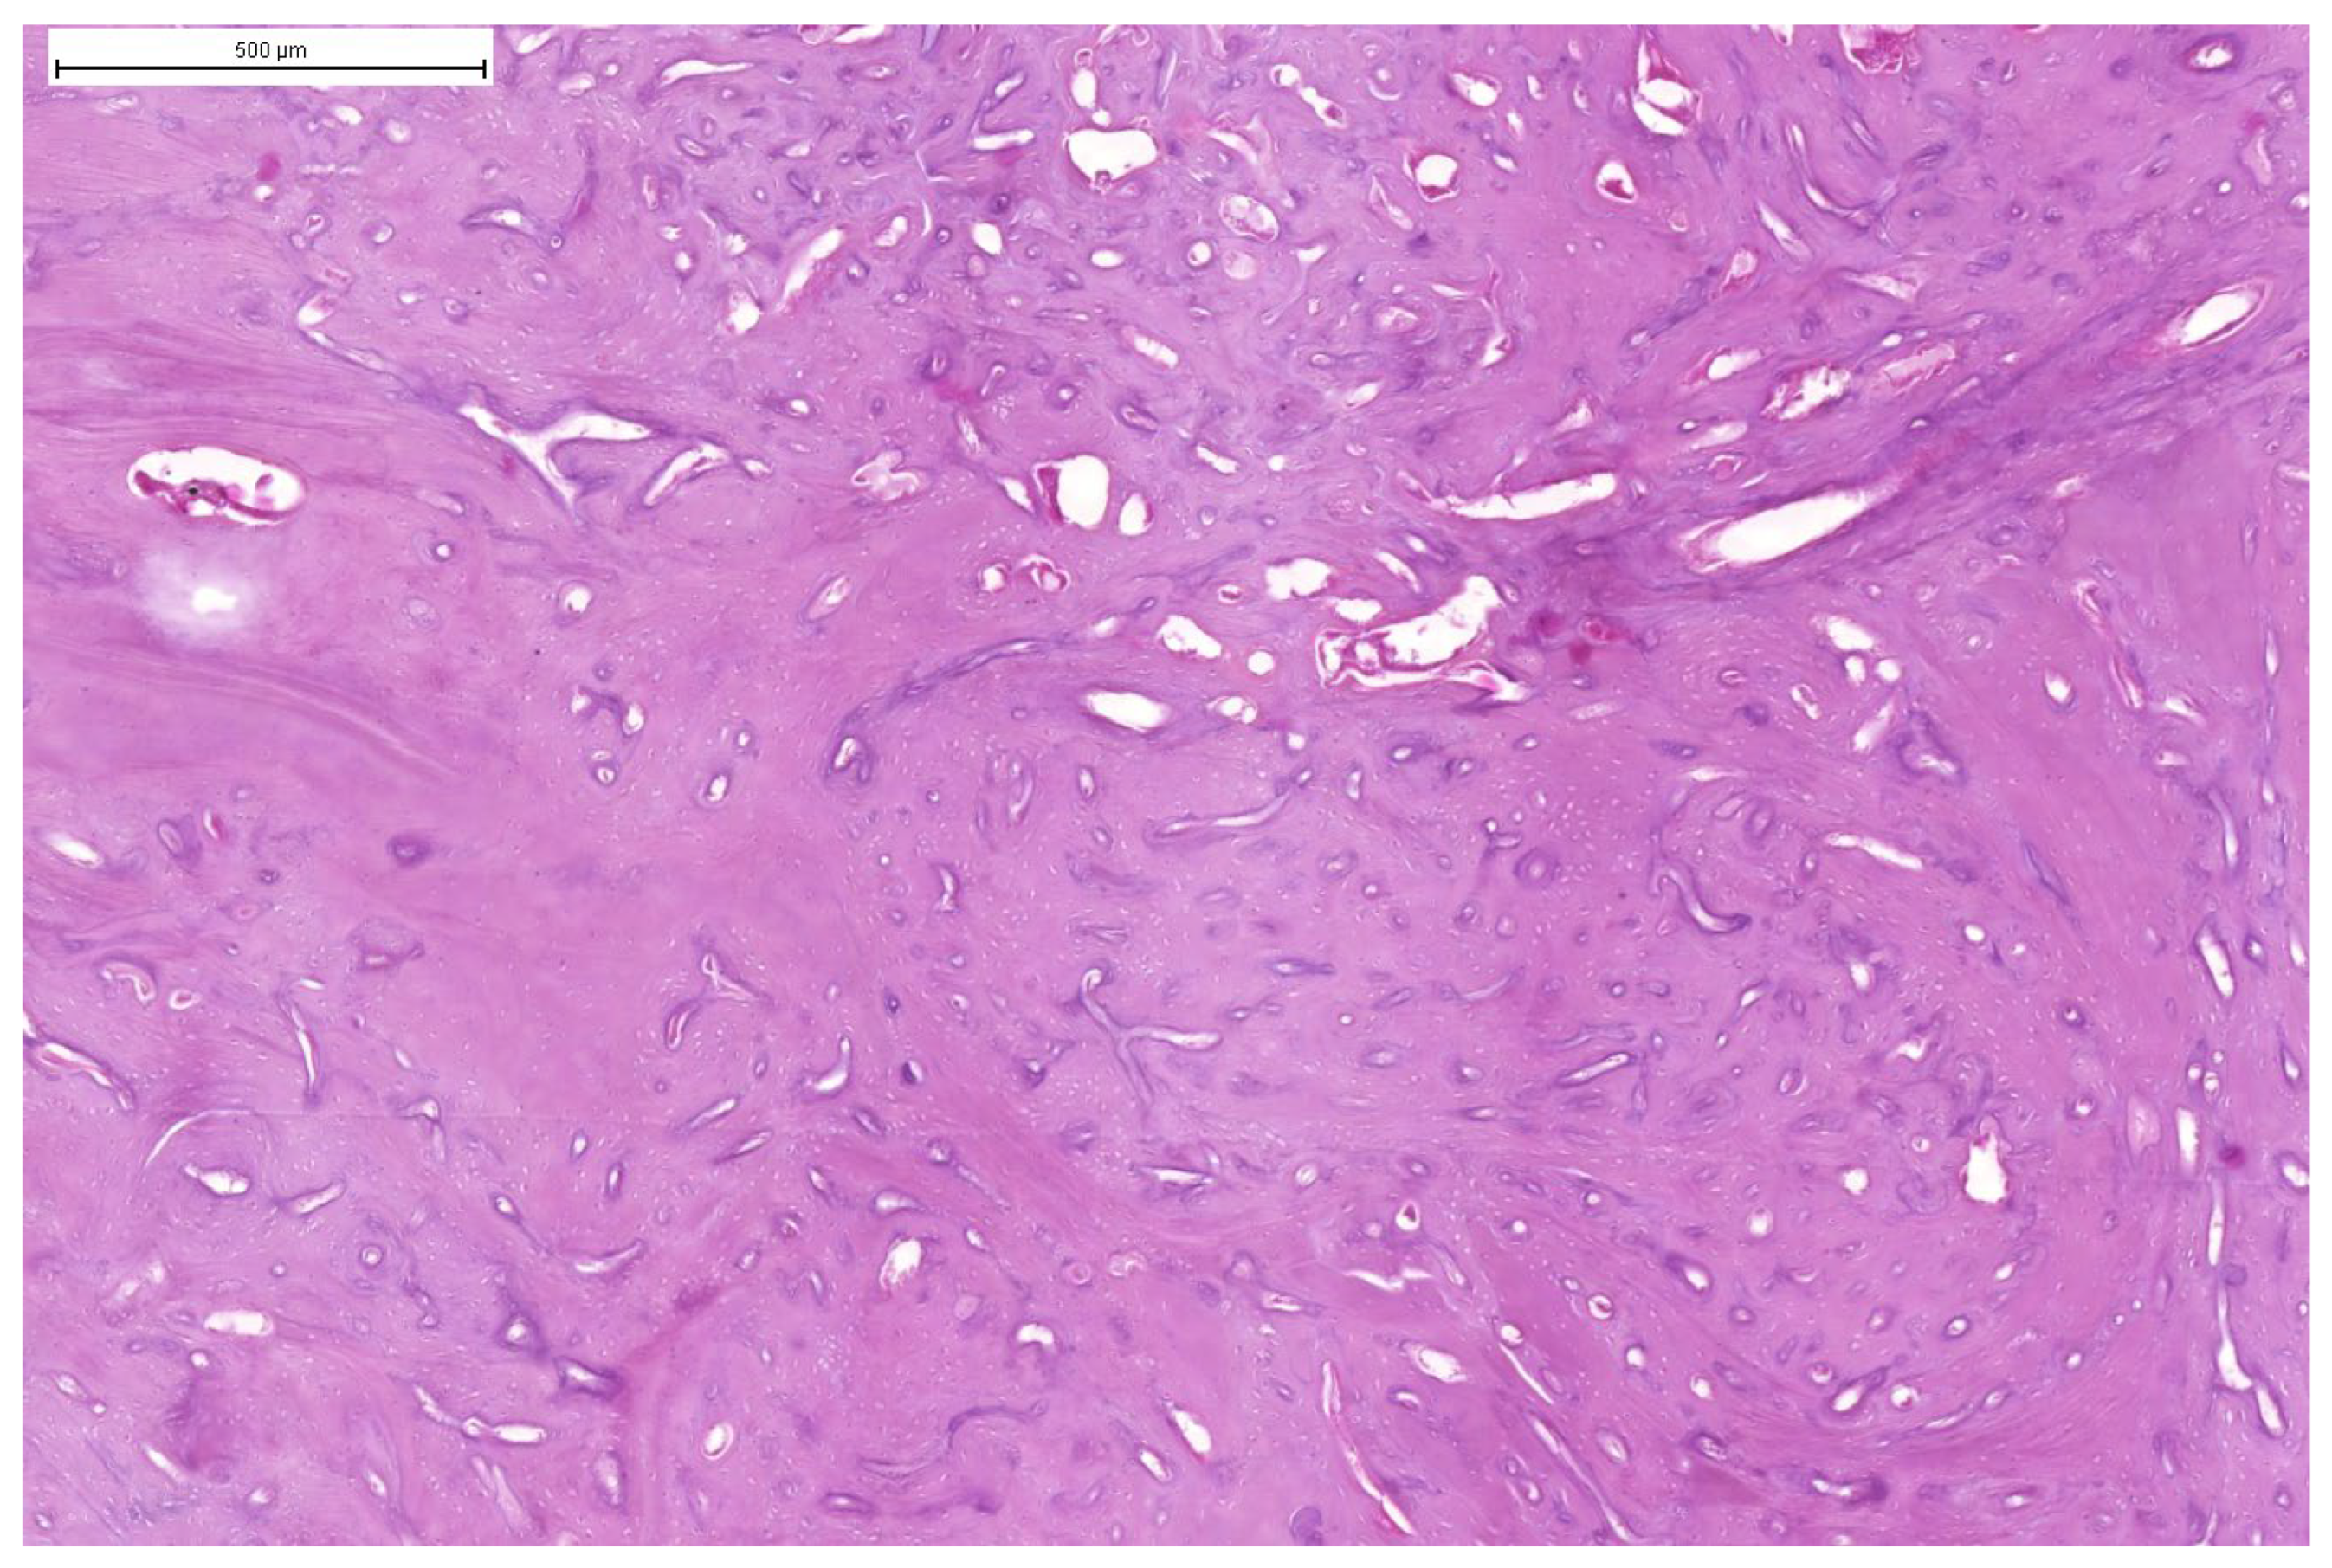

3.3. Results of Microscopic Examination